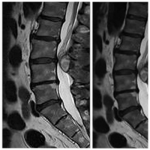

Factores asociados a la recurrencia de las fracturas vertebrales tras una vertebroplastia en el adulto mayor

Hugo J. Kurtz Goritz, Leonardo F. Benolol, Juan Jesus Mazzeo, Cristian A. Angeramo, Eduardo P. Eyheremendy

¿Se asocia el tropismo facetario con la enfermedad degenerativa y la lateralidad de las protrusiones?

Damián Bendersky, Mauro Ormeño Figueroa